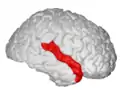

Position of superior temporal gyrus (shown in red).